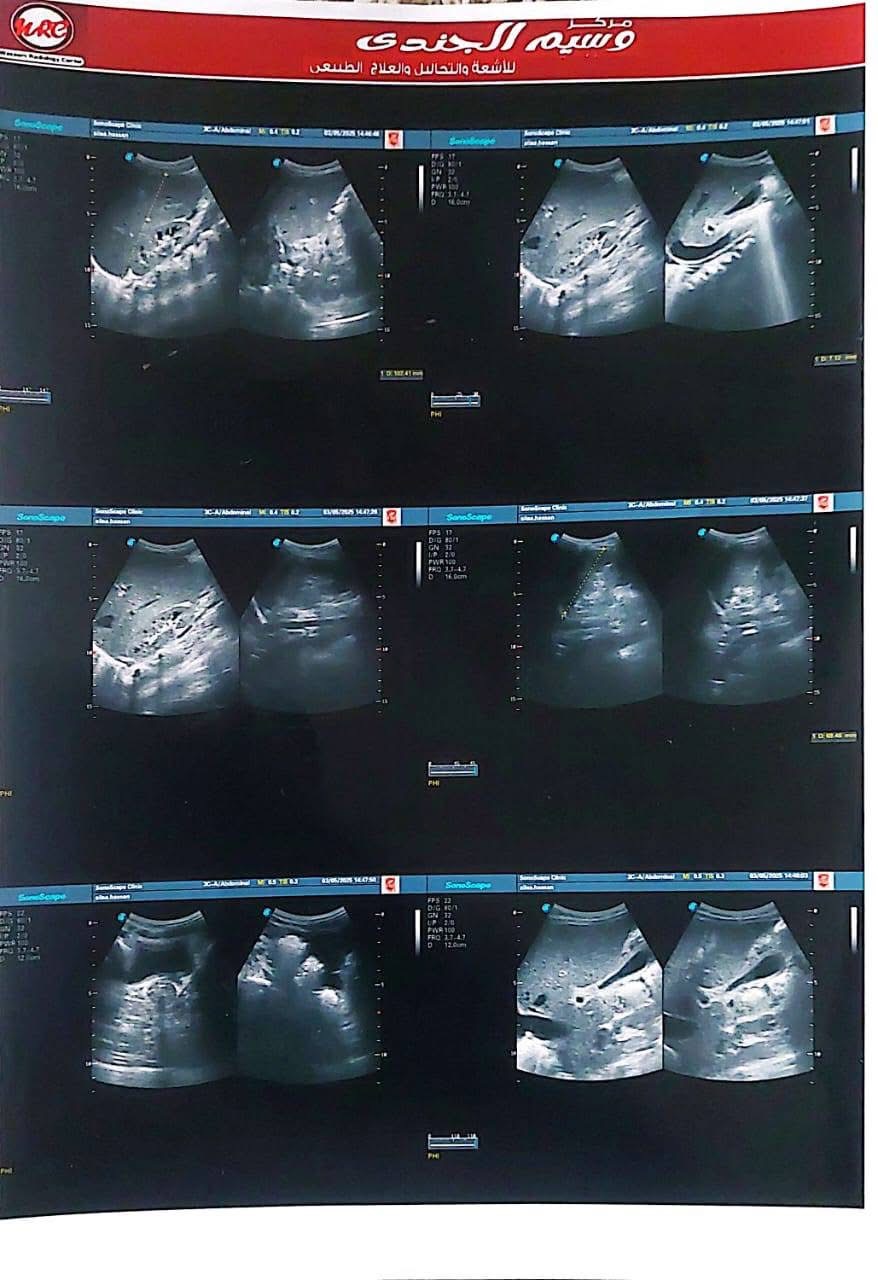

ناشدت أسرة الطفلة عليا حسن، البالغة من العمر أربع سنوات ونصف، الجهات الطبية المعنية وعلى رأسها مؤسسة مجدي يعقوب لأمراض القلب ومستشفى الناس، للتدخل العاجل لإنقاذ حياة ابنتهم، التي تعاني من فشل شديد في عضلة القلب وتضخم كبير بالقلب، ما أدى إلى مضاعفات صحية خطيرة شملت الكبد وأجهزة أخرى من الجسم.

وكشفت أحد أقارب الطفلة تفاصيل الحالة الصحية لها، قائله "عليا حسن بنت خالي 4 سنوات ونصف الأسبوع الماضي جالها استسقاء في معدتها كبير والبنت مكنتش عارفة تتنفس ولا قادرة تتحرك وتعب شديد، لفوا كتير لحد ما عملوا إيكو على القلب وطلع في ضعف شديد في عضلة القلب وتضخم في القلب جامد، ودا طبعا أثر على كل وظائف الجسم وأثر على الكبد بشكل ملحوظ".